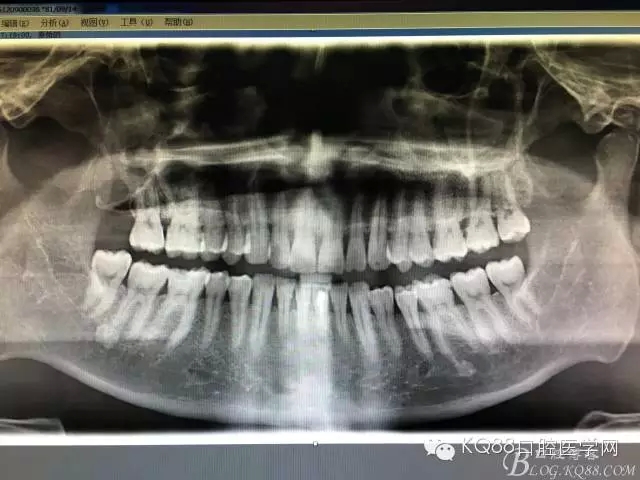

圖2.術(shù)前做全景片影像檢查:18頰舌向高位阻生,牙冠位于17牙根的正上方,懷疑18位于上頜竇內(nèi)。

圖3.加拍CBCT影像檢查:18位于上頜竇內(nèi),并導(dǎo)致右側(cè)上頜竇粘膜炎性增生。18牙冠的合面朝向頰側(cè)。并且與17頰根緊密相鄰。